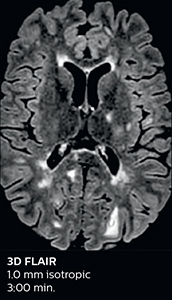

Ingenia Elition 3.0T with Compressed SENSE

3D FLAIR 1.0 x 1.0 x 1.0 mm* 2:50 min.

3D TSE T1w 1.0 x 1.0 x 1.0 mm* 2:10 min.

The abbreviated MS protocol for brain is only around 9 minutes, so in case of suspected multiple sclerosis, one or two more advanced sequences may be added, such as PSIR (phase sensitive inversion recovery) or susceptibility-weighted sequences to help us make more confident diagnoses in these inflammatory cases.

In this example, the optional 3D multishot susceptibility weighted sequence with 0.6 mm isotropic voxels is 2 lesions with a central vein sign (arrows) and one lesion with a phase-rim sign (arrowhead). The total scan time, including SmartBrain and axial PD/T2 3mm, is 11:10 min. and is 18:30 min. with the optional 3D PSIR and 3D SWI multishot included.

“We used to have long examination times for certain types of patients, a few lasting more than 40 minutes,” says Dr. Savatovsky. “What is remarkable, is that now all these examinations are below 30 minutes, which opens up opportunity to add more sequences when needed. It’s really hard to keep a patient for more than 40 minutes in the scanner, but because we have now cut scan times by at least 10 minutes, we can add more sequences without making the exam too long. And this is where the new system helps us make a difference. Examples include our examinations for informing brain tumor classification or giant cell arteritis workup, or for intracranial wall imaging – so in patients where we need several advanced sequences or high resolution sequences.” “We added three additional sequences in our brain neoplasm classification exam: a 3D SWI sequence, APT and ASL on top of 3D morphologic sequences, an isotropic DSC (dynamic susceptibility contrast) and multivoxel spectroscopy. I think that in patients that need a classification for brain mass, for example, we can provide a more detailed and confident diagnosis than before, allowing the clinicians to decide for either a medical workup if no tumor is suspected, or for neurosurgery as soon as possible if a neoplasm is suspected.” “In multiple sclerosis patients, we increasingly include a multishot susceptibility sequence [3] in our routine cases, thanks to the shorter scan times. Our abbreviated MS protocol for brain is around 8 to 9 minutes, so we can ask for one or two additional sequences to visualize the central veins, or to get an additional contrast to better depict posterior fossa lesions. In cases of white matter lesions of unknown significance on FLAIR images, for example when we see high signal hyperintensities in the brain, we can add on more advanced sequences such as PSIR (phase sensitive inversion recovery) or susceptibility-weighted sequences to help us in distinguishing between MS and nonspecific or vascular abnormalities in these inflammatory cases.”